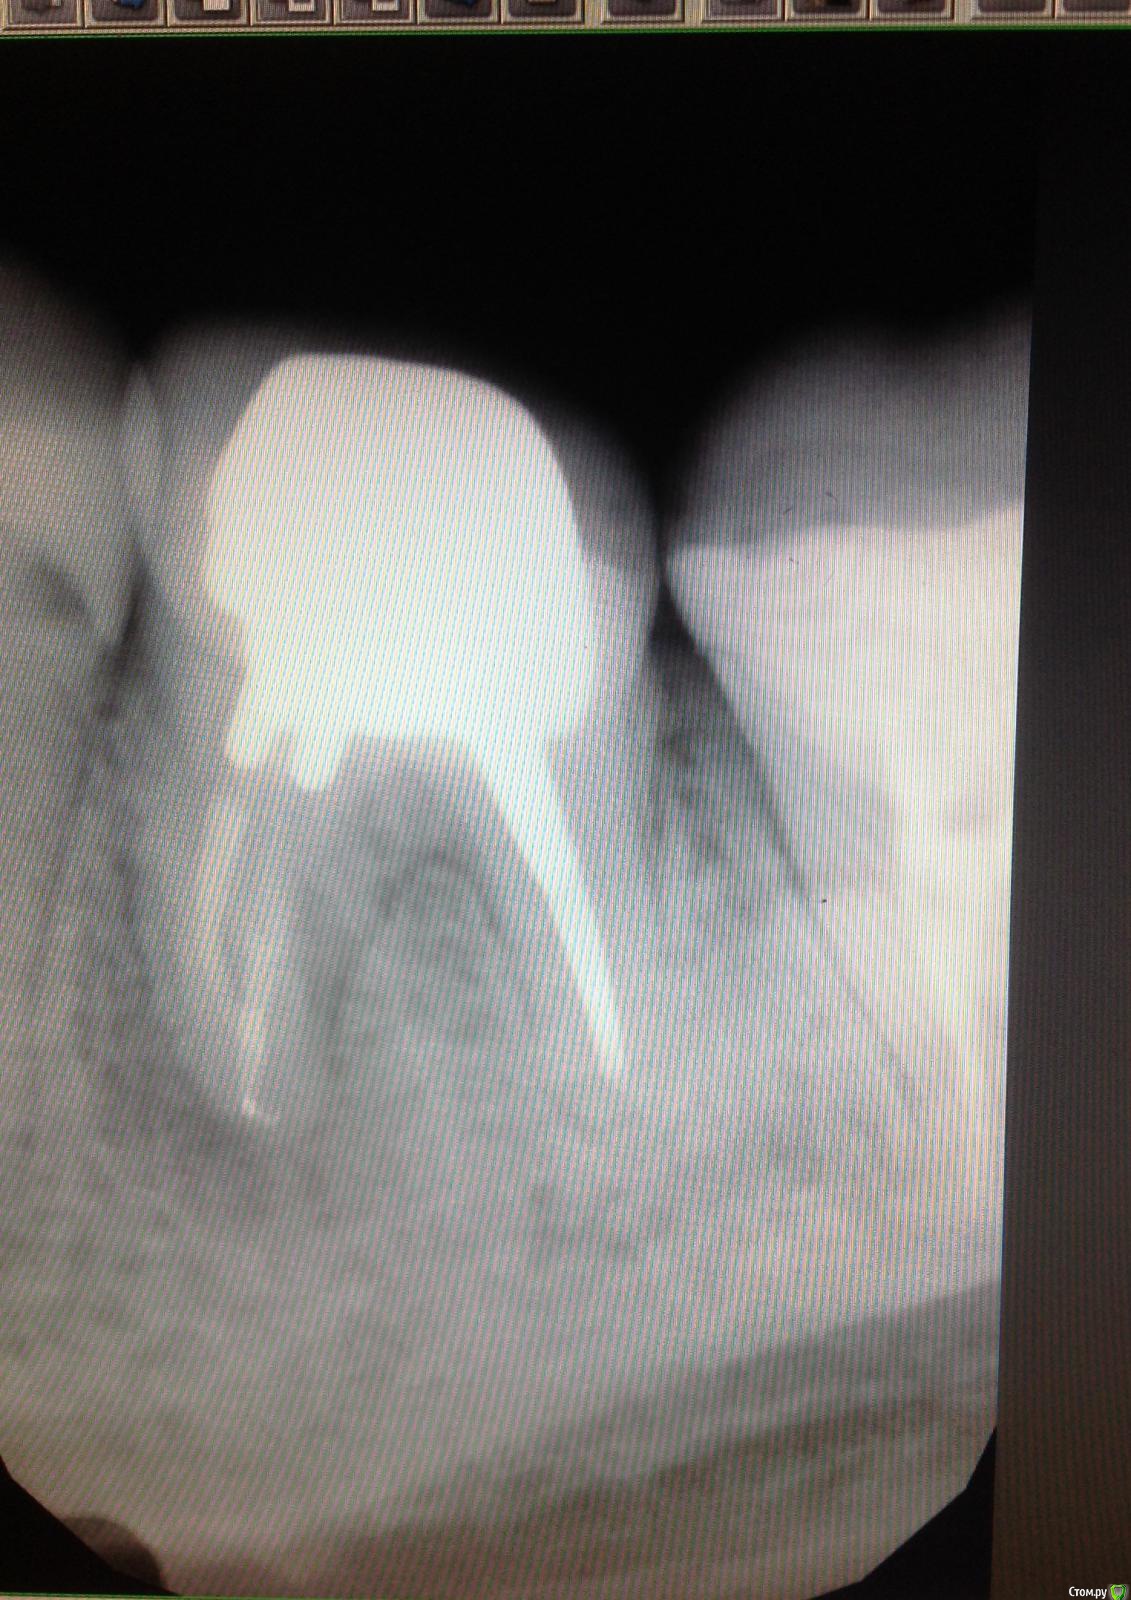

Сашуля Опубликовано 8 декабря, 2016 Поделиться Опубликовано 8 декабря, 2016 (изменено) Здравствуйте уважаемые стоматологи.Очень хочется получить совет.Имею хронический периодонтит. Температура 37,3 постоянно, впрочем, это мне не мешает.Первое фото. Когда обнаружили периодонтит. 2013 год.Второе фото-в процессе лечения.Мне запломбировали каналы, постави вкладку, налили пластиковую временную коронку и отправили в свободное плавание. Зуб никак не беспокоил.Наблюдалась, делала снимки с определённой периодичностью. Зуб не беспокоил.Сейчас настал решающий момент. Последние два снимка были сделаны сегодня. Сторона с проблемным зубом ноет, непонятно, что это болит, толи соседние зубы, толи периодонтит беспокоит. Боль усиливается к вечеру. При надавливании на проблемный зуб острая боль. При внешнем осмотре всё в норме.Вообще грозятся удалять или сделать Гемисекцию. Чего мне ожидать, может быть можно по данным снимкам чтото выяснить.Спасибо. Изменено 8 декабря, 2016 пользователем Сашуля Ссылка на комментарий

Сашуля Опубликовано 8 декабря, 2016 Автор Поделиться Опубликовано 8 декабря, 2016 очень сомневаюсь На снимке 2013 года и сегодняшнего дня, мне кажется, нет разницы. Добавила ещё одно фото сегодняшнего снимка. Но если Вы, как специалист, рекомендуете сделать внимание и на этом зубе, не могу не согласиться. Ссылка на комментарий

IvanK Опубликовано 8 декабря, 2016 Поделиться Опубликовано 8 декабря, 2016 Считаю, что изменения есть 1 Ссылка на комментарий